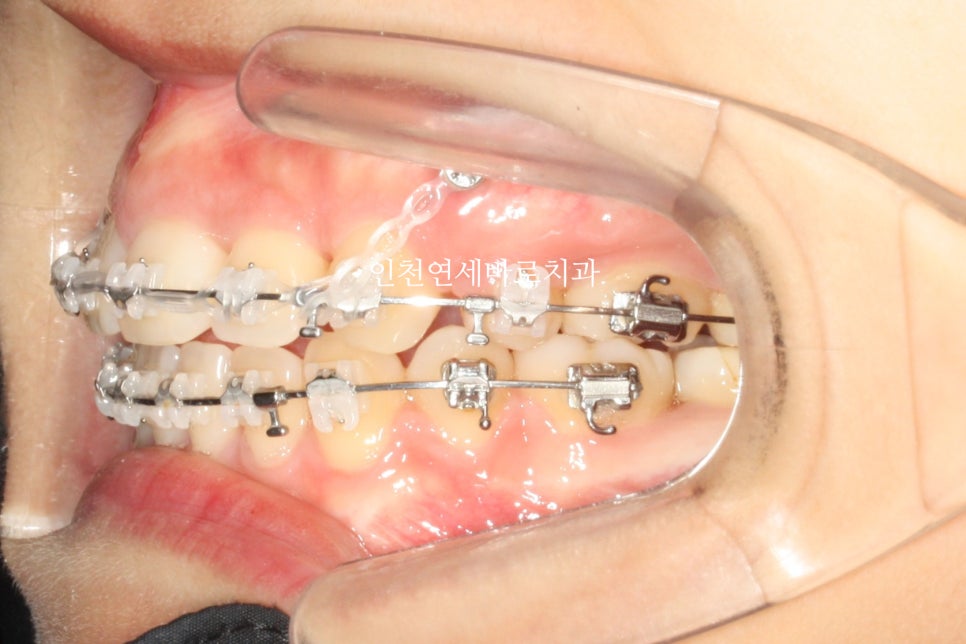

치료가 마무리 되었습니다

안모의 변화가 가장 중요하죠

입술이 들어갔다 덜 들어갔다가 아니라,

자연스럽게 다물어지는가가 중요한 포인트입니다

교정 후 입술이 조금 더 자연스러워졌습니다.

발치 비발치를 교과서에 나오는 기준으로만 정하진 않아요

환자분의 안모를 먼저보고 조화로운 교합을 맞추기 위해 노력하죠.